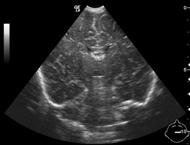

Malrotation-volvulus. During the normal development of the intestinal tract, the intestinal loops make three 90 degree clock-wise rotations around the mesenteric superior artery (MSA.) If this rotation only partially occurs during the embryonic development the intestines remain in a non-rotational or malrotational position, the mesenteric root will be shorter and the cecum will be weakly attached. This anatomic positioning can be symptom free throughout a lifetime, but it predisposes for volvulus. Volvulus can occur at any age, but it is most frequent in the first months of life, when it abruptly occurs with acute bilious vomiting. In this state the intestines around the mesenteric root twist, end up in a complete obstruction that can lead to a rapid death of the intestines. Ultrasonography can depict the mesenteric superior vein (MSV) coiled up around the MSA, so called “whirlpool”-sign.

14. “Whirlpool” sign The mesentery and the superior mesenteric vein, as it coils around the superior mesenteric artery. Volvulus. US exam.

Image

15. Contrast material empties the stomach slowly, small intestines are found on the right side of the abdomen. Malrotation-volvulus.